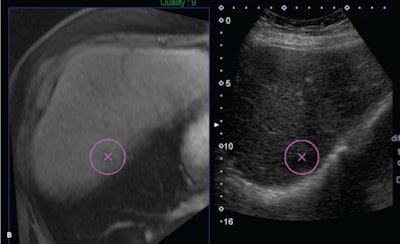

Software that fuses ultrasound images with MRI or CT studies can accurately guide liver biopsies for lesions that are hard to see on conventional ultrasound, yielding similar accuracy as CT-guided biopsy as well as some key benefits, according to an article in the June issue of the Journal of Ultrasound in Medicine.

In a retrospective study, a research team led by Dr. Yasmine Ahmed of University Hospitals Case Medical Center in Cleveland evaluated the performance of ultrasound fusion software, which enables interventional radiologists to view a patient's previously acquired CT or MR images side by side with the live ultrasound exam as they perform guided biopsies. Compared with CT-guided biopsy, ultrasound fusion-guided liver biopsy had a similar diagnostic yield, but it could be performed in about half the time and without exposing patients to additional radiation, according to Ahmed.

"When a limited screening evaluation of the liver using B-mode ultrasound showed lesions that were either invisible or hardly visible, a decision was made to switch to ultrasound fusion guidance instead," the authors wrote.

Matching anatomic landmarks on the real-time ultrasound feed with the fused CT/MR image took an additional five minutes for each procedure, according to the group.